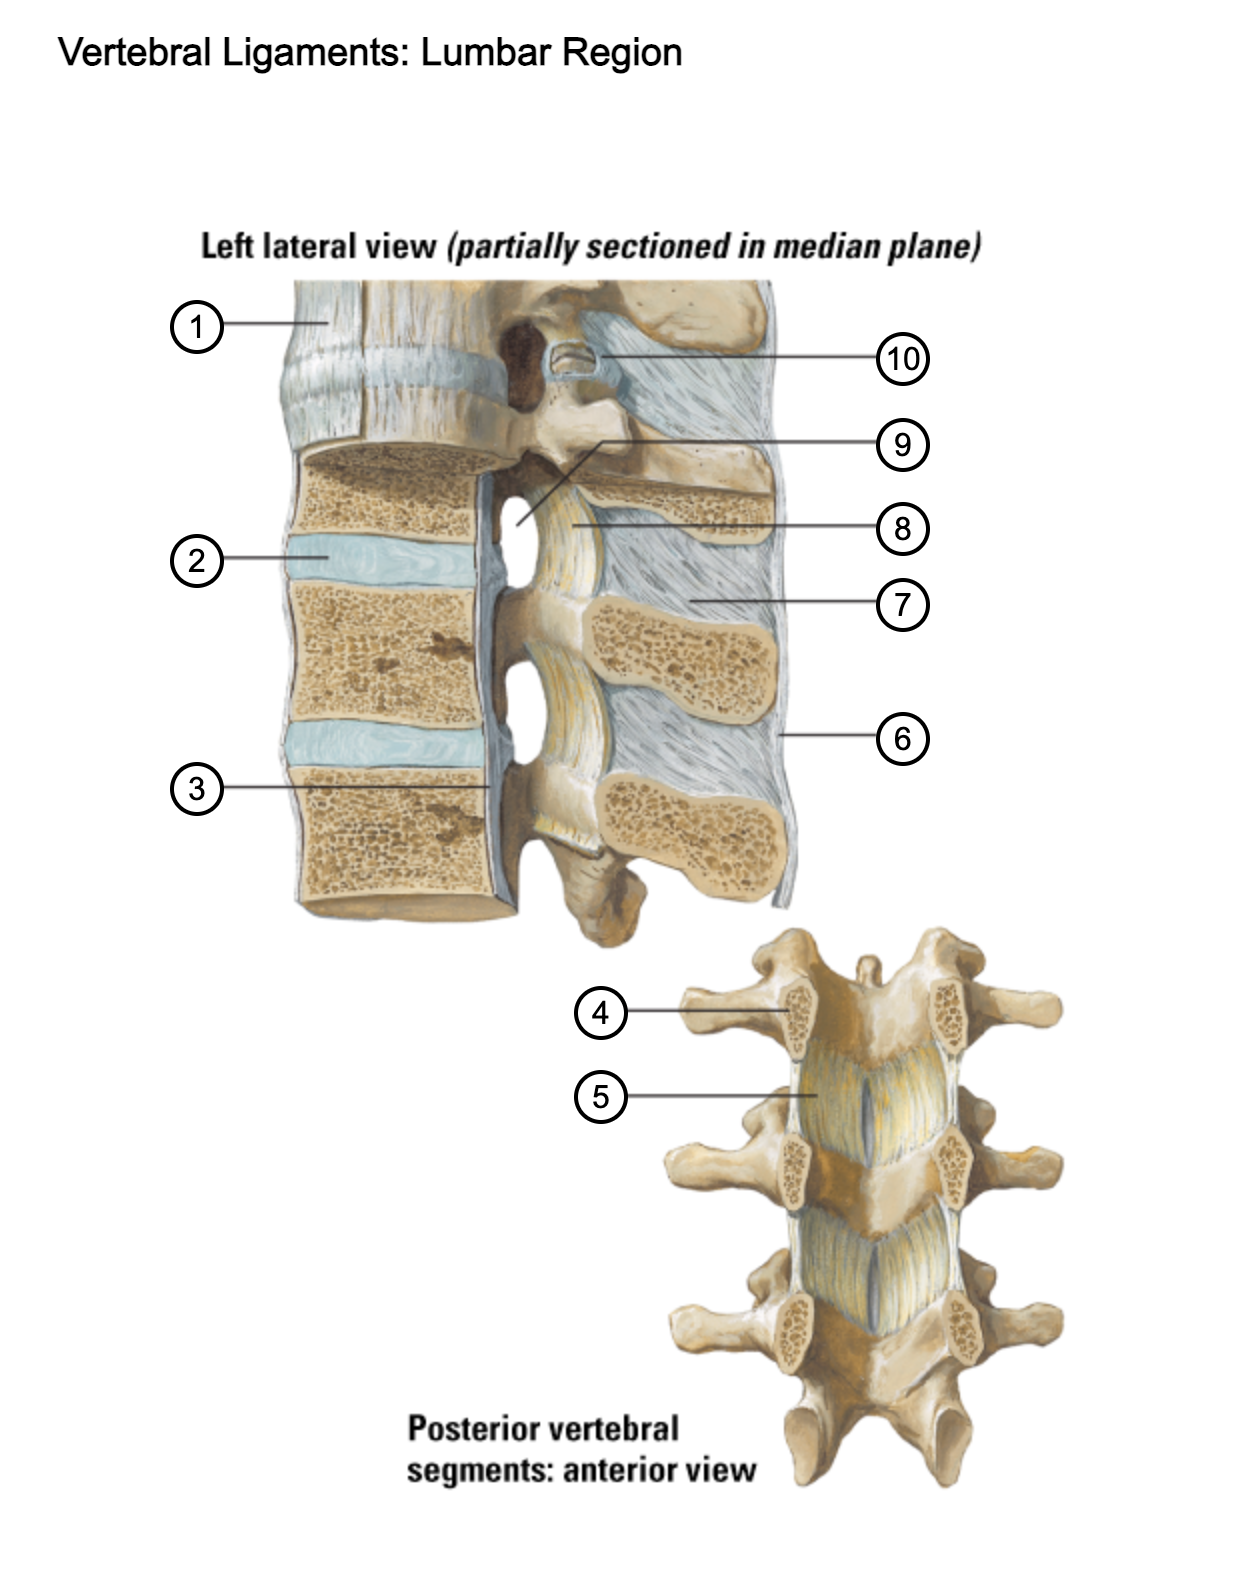

1

anterior longitudinal ligament

2

intervertebral disc

3

posterior longitudinal ligament

4

pedicle (cut surface)

5

ligamentum flavum

6

supraspinous ligament

7

interspinous ligament

8

ligamentum flavum

9

intervertebral foramen

10

capsule of zygapophysial join (partially opened)